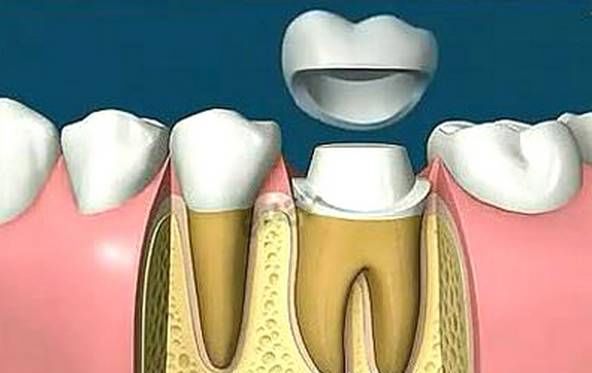

为什么做完根管治疗后,我们要做烤瓷牙冠?

1、根管治疗是以药物以及器械的操作来将根管内的残渣以及细菌尽可能地清除消毒干净。然而,这样的消毒过程如果要认真的进行,却必须去除掉不少被细菌感染的牙齿,以及不得不修整的牙体组织。所以大部分的牙齿一旦进行根管治疗,则可能不太足够支持咀嚼的力量而可能断裂,单纯用材料已经没法恢复功能,即使能恢复长远效果也不好。

2、经过根管治疗后的牙齿失去了来自牙髓的营养供应,就像失去树根的树木一样,慢慢枯萎变的很脆弱,造成牙齿的脆性增加,易劈裂。

3、因为需要进行根管治疗的牙齿一般已是龋病(虫牙)、缺损很大,这时虽然根管治疗完成,但是其所剩的牙体组织是很脆弱的,非常容易折断、裂开,失去正常的功能,单纯用材料已经没法恢复功能。

那既然如此,何不在一开始做完根管治疗后,直接做个烤瓷冠或是全瓷冠,直接把牙齿保护起来呢,至少一开始保护的还是一个完整牙!

现在非常普遍的烤瓷牙冠外形逼真,不变色,使用时间长,能够更好的保留经过根管治疗后的牙齿。烤瓷牙冠基本分两种:一种是金属的,一种是全瓷的。